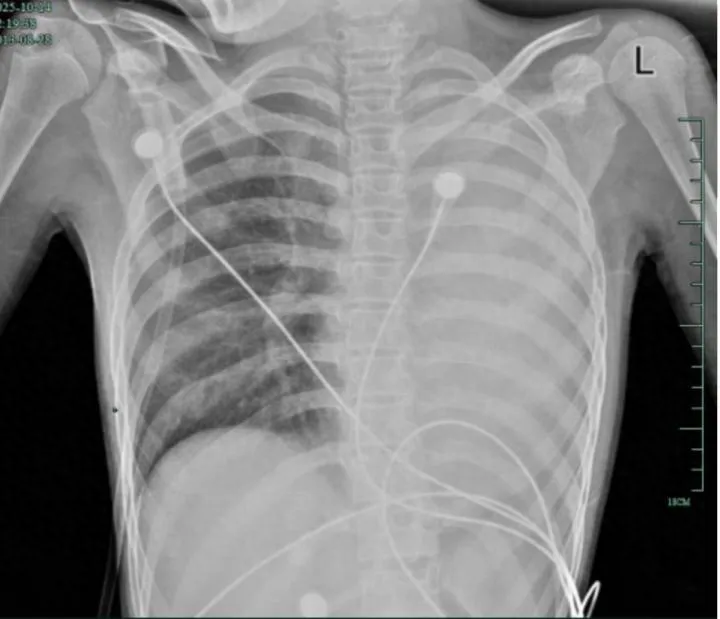

治疗前,左肺呈“白肺”状态

入院后,她很快出现呼吸急促、胸闷胸痛,只能靠 5L/min 的面罩吸氧维持血氧,胸片显示左肺已完全呈“白肺”改变,肺部炎症进展迅猛。